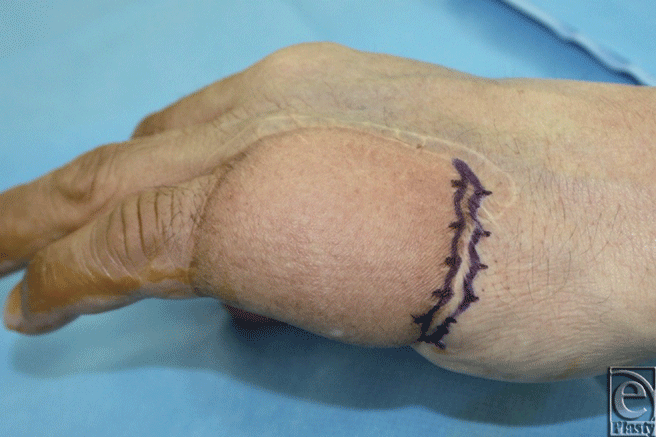

We would like to present the use of the S-plasty method for revising the inset of a flap. Occasionally, the inset of a flap results in a depressed scar at the junction between the flap and the normal skin. This scar is further accentuated in a bulky flap. An S-plasty was designed over the depressed portion of the scar (Fig. 1). The S-plasty involves making a series of small-wave like incisions that are approximately 0.5 to 1.0 cm in length. The scar measured 6.5 cm preoperatively and the immediate postoperative length was 8 cm. Figure 2 shows the late postoperative appearance.

| Figure 1. Design of S-plasty over the depressed scar at the junction of abdominal flap and normal skin. |